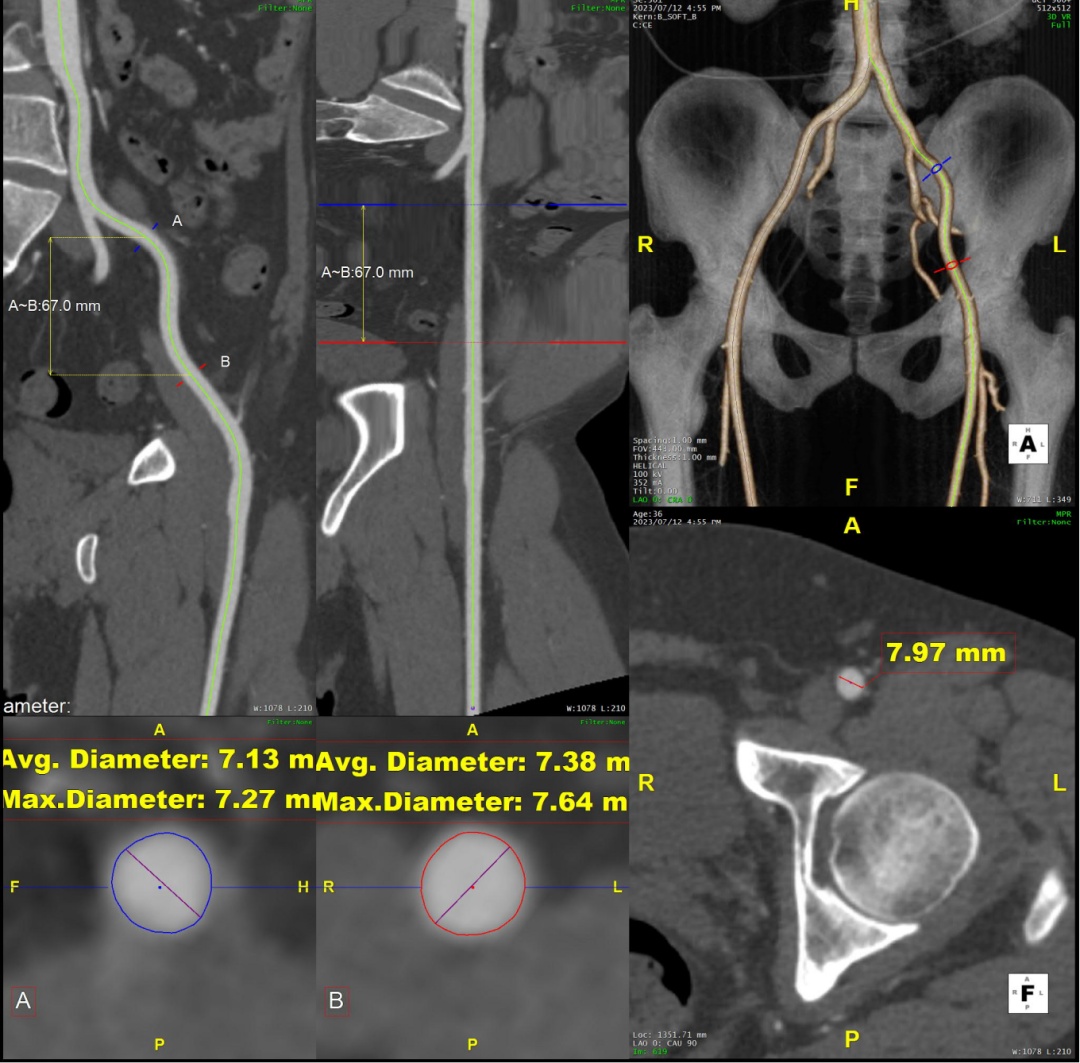

术前CTA评估与测量

术前CTA提示主动脉夹层(Stanford B型,Debake llI型),主动脉弓及降主动脉瘤样扩张,累及左锁骨下动脉起始段,管径最粗约7.4cm,夹层初破口位于降主动脉起始段,向下累及至腹主动脉(约平胸12椎体水平),真腔小,假腔大,腹腔干发自混合腔,肠系膜上动脉、下动脉,双肾动脉均起自真腔,双肾灌注未见差异。

术前三维重建

术前CTA详解:

病例特点

1. 弓型陡峭,成角;

2. 自左颈总后缘小弯侧锚定区不足1cm;

3. 巨大破口,约33mm,病变累及至腹腔干平面。